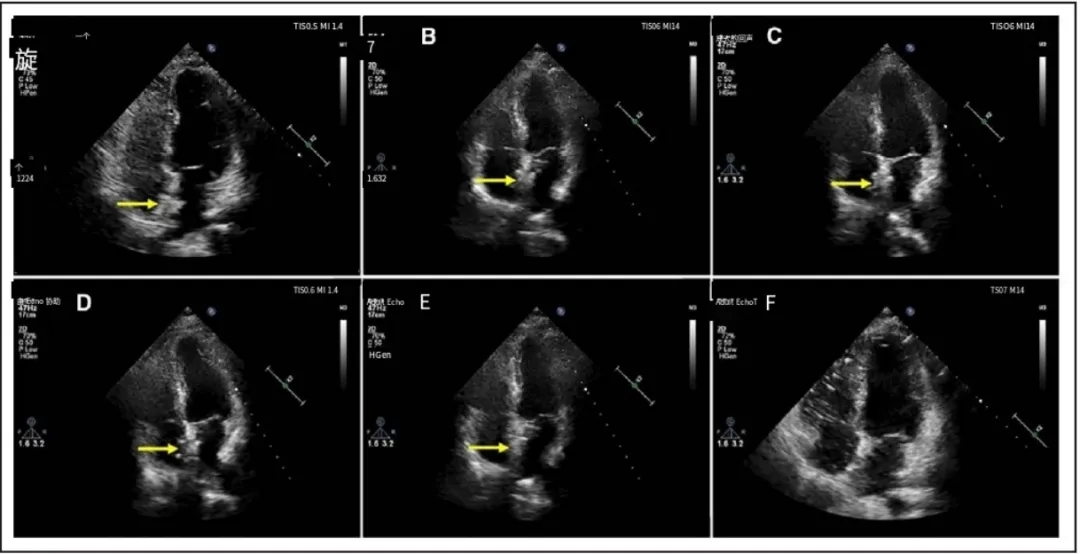

植入6个月后,超声心动图显示新型可降解卵圆孔未闭封堵器表现为自周围心内膜突出的高回声区。至24个月随访时,该封堵器与周围心内膜处于同一水平(图4;视频S3)。在1、3、6、12和24个月随访时,左盘在经胸超声心动图测量的高回声区降解比例分别为92.59%、83.41%、64.62%、16.41%和0%,而右盘分别为92.43%、83.44%、66.26%、17.37%和0%。在每个随访时间点,左、右盘突出的高回声区的降解比例具有可比性,两侧之间未观察到统计学显著差异。至植入后24个月,所有患者经胸超声心动图(TTE)下均未再观察到代表新型可降解封堵器的高回声区,提示封堵器已完全降解(视频S3)。

图4. TTE下生物可降解封堵器在术后24个月随访期间的形态学特征变化

黄色箭头所示为生物可降解封堵器。出院前(A)、术后1个月(B)、3个月(C)、6个月(D)、12个月(E)及24个月(F)随访时均进行了经胸超声心动图四腔心切面检查。术后24个月时,封堵器已完全降解。